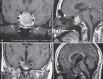

Results: Four out of 82 male MPRL had SM = 4.87%. Three consulted for SM symptoms. SM was confirmed in Infectious Diseases department, but only one had rhinorrhea. Hormonal assessment and cerebral magnetic resonance imaging pleaded for aggressive prolactinomas. After antibiotics, SM was sterilized. Then, MPRL were treated with bromocriptine, which normalized prolactin and reduced PT. SM never relapsed. The 4(th) case was hospitalized for a large multidirectional prolactinoma invading and/or arising from the skull base. He was operated on 3 times and then he was given Bromocriptine. After 3 months, he had rhinorrhea and then SM which was successfully treated by antibiotics. SM never relapsed after tumor reduction.